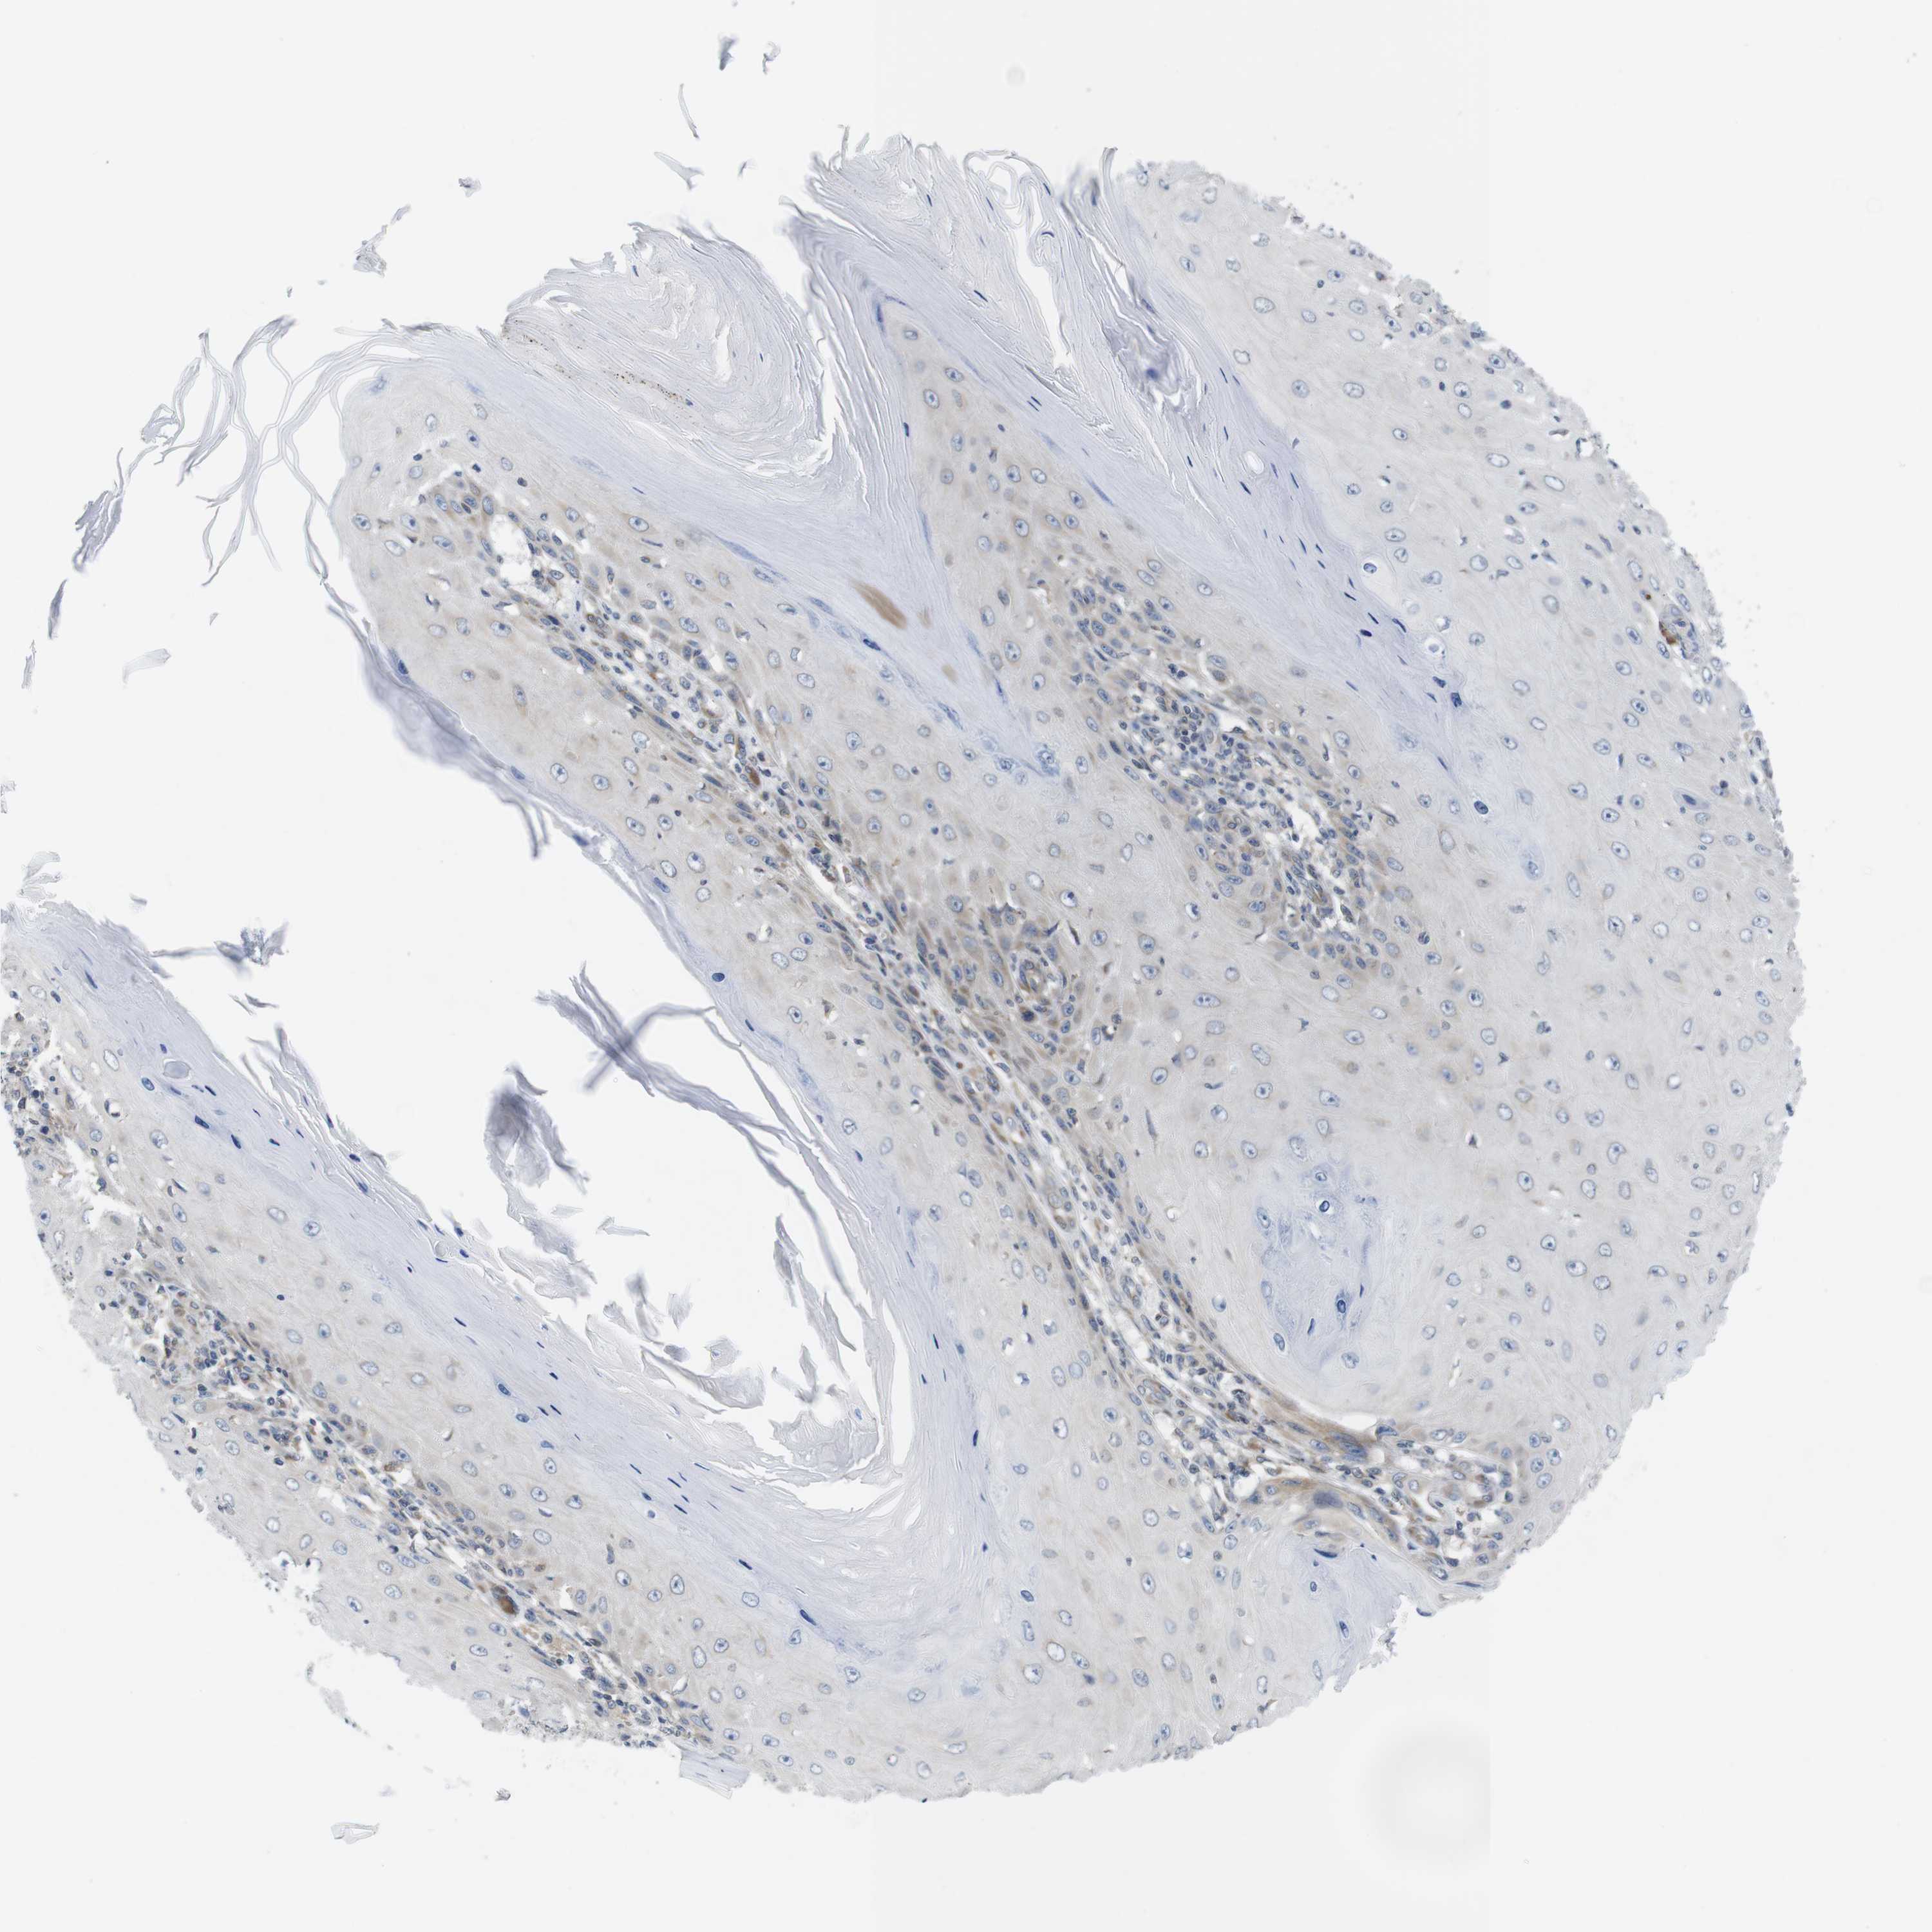

Basal cell and squamous cell cancer

SKIN CANCER - Protein expressioni

A mouse-over function shows sample information and annotation data. Click on an image to view it in a full screen mode. Samples can be filtered based on level of antibody staining by selecting one or several of the following categories: high, medium, low and not detected. The assay and annotation is described here.

Each image is clickable and will lead to virtual microscopy that enables deeper exploration of all samples and also displays staining intensity scores, fraction scores and subcellular localization as well as patient and tissue information for each sample.

Antibody HPA015968

Basal cell carcinoma